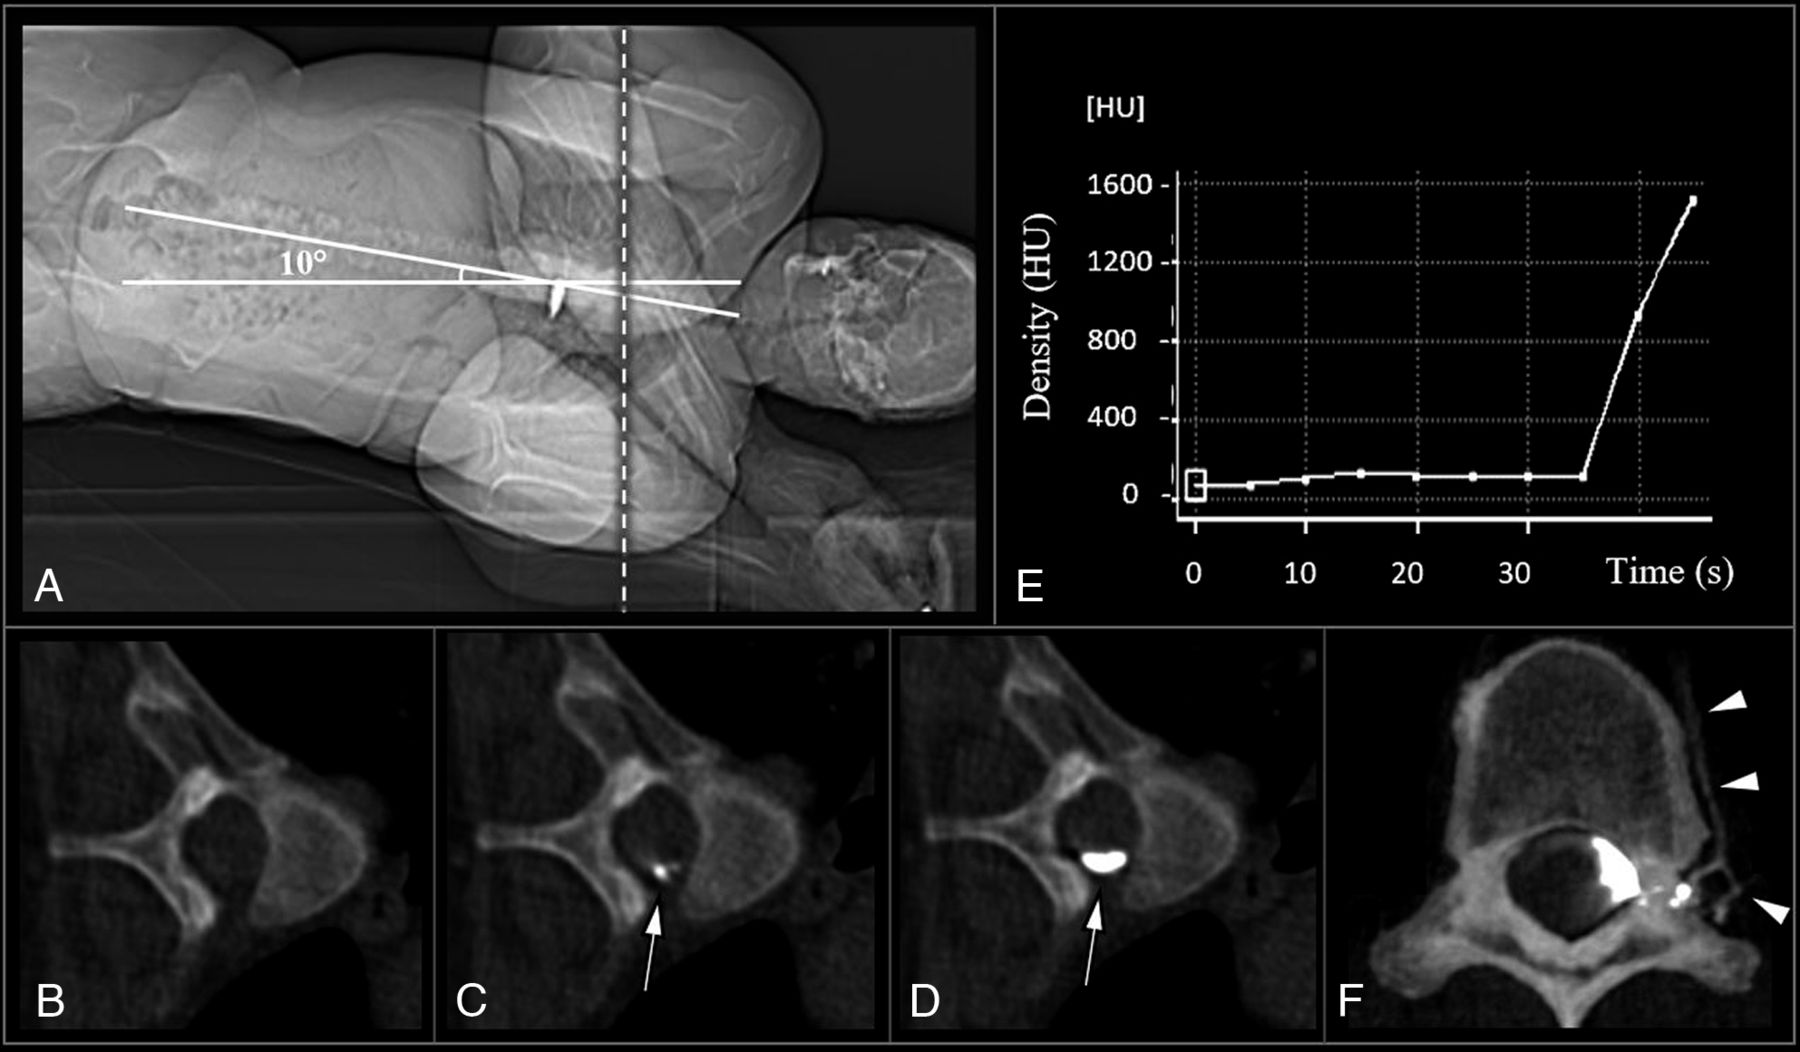

Diagnostic Yield of dCTM-BT, Stratified by Brain MRI Findings

Using the dCTM-BT technique, stratified by the Bern SIH score, CVF was detected in 100% (22/22) of the patients who had a high Bern SIH score, 14% (1/7) of those who had an intermediate score, and 0% (0/19) of those who had a low score (Figure 3). On the ROC analysis shown in Figure 3, the area under the curve for the association between the Bern SIH score and the identification of CVF on the dCTM-BT was 0.99 (95% CI, 0.98–1.00). The maximum value of the Youden index was at a score of ≥5. A Bern SIH score of ≥5 had a 96% sensitivity and a 100% specificity for the presence of CVF.

Bar chart illustrating the number of patients with CVF identified on dCTM-BT, across Bern SIH scores. The Bern SIH score was calculated based on the brain MRI, categorizing the probability of a spinal CSF leak as low (score of 0–2), intermediate (score of 3–4), or high (score of 5–9).